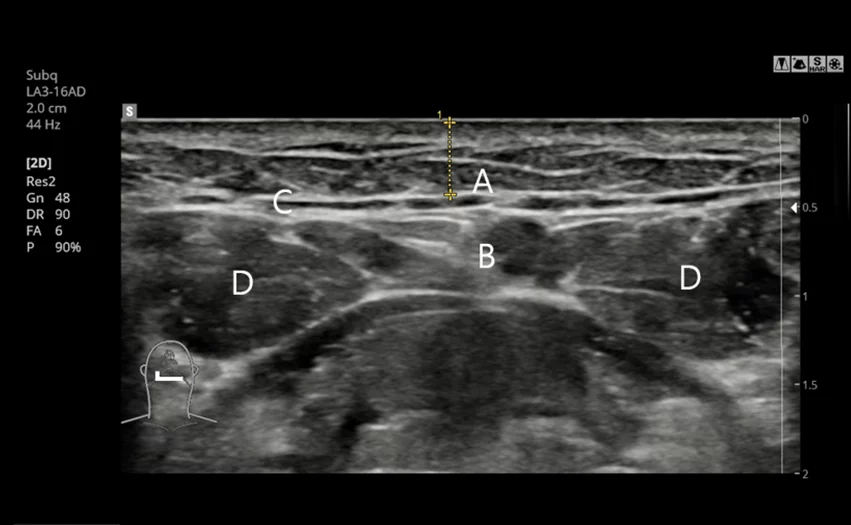

5. 手術前のCTと超音波精密カスタム診断

CT撮影および超音波検診で唾液腺の位置と大きさを精密に分析し

必要に応じてカスタマイズされた唾液除去手術進行